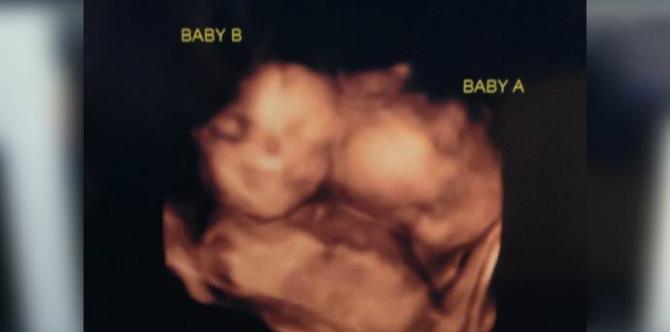

Couple continue pregnancy of MoMo twins despite considerable risks

"The umbilical cord while she’s sleeping is right in front of her face,” Jessica admitted. “They monitor her three times a day.”

During the couple’s first pregnancy checkup they found out that they’re awaiting a rare set of ‘MoMo’ twins, a case in which the babies share the same placenta and amniotic sac.

“He almost fainted,” Jessica says in an ABC 8 report. “We were just staring at the screen and we were like, ‘there are two heads in there!’”

According to Peter Genaris, an OB Hospitalist with St. Mary’s, there’s an increased risk of cord entanglement, which means that both babies have a high chance of getting tangled in each other’s cords.

“The umbilical cord while she’s sleeping is right in front of her face,” Jessica admitted. “They monitor her three times a day.”

Not only that, doctors said this creates a 20 percent risk of mortality for the babies throughout the pregnancy.

Photo credit: ABC

In fact, mono mono twins occur only once in every 10,000 pregnancies.

Monoamniotic twins are identical twins that share the same amniotic sac within their mother’s uterus.

Monoamniotic twins are always identical, always monochorionic and are usually termed Monoamniotic-Monochorionic (“MoMo”) twins. They also share the placenta, but have two separate umbilical cords.